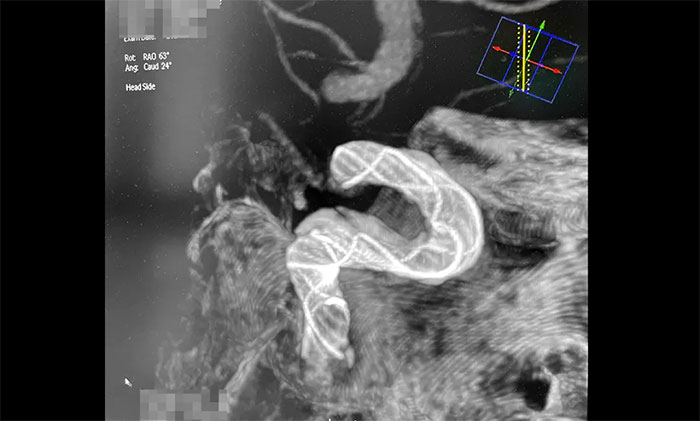

接下來,左頸內動脈海綿竇段、床突段多發(fā)動脈瘤處理極具挑戰(zhàn)。由于C5、C6、C7段血管極度迂回曲折,類似“N”形,從C4、C5到C6之間的血管約成45°銳角,從C6至C7之間又是約30°銳角,可謂“山路十八彎”,而導絲又是極軟,每向前推進一毫米,都非常艱難。這種介入手術對術者的技術要求非常高,如果支架貼合不好,打開不良,還需要用導絲蠕動“按摩”,讓支架重新回到血管壁上。

術中,席剛明教授、王貴平博士克服血管迂曲困難,經(jīng)過多次嘗試,多次球囊擴張、“按摩”后,最終順利釋放密網(wǎng)支架至左頸內動脈眼動脈段、左頸內動脈床突段、左頸內動脈海綿竇段。造影及3D造影見,動脈瘤瘤內造影劑明顯滯留,左頸內動脈、左大腦前動脈顯影可,載瘤動脈通暢,獲得了理想的血管重建。復查造影,左頸總動脈造影見左頸總動脈、左頸內動脈、左大腦前動脈顯影可。CT見支架打開貼壁滿意,XperCT未見顱內出血,手術圓滿完成,順利拆除“不定時炸彈”并打通大腦生命線。

▲ 血管極度迂曲,為手術帶來挑戰(zhàn)